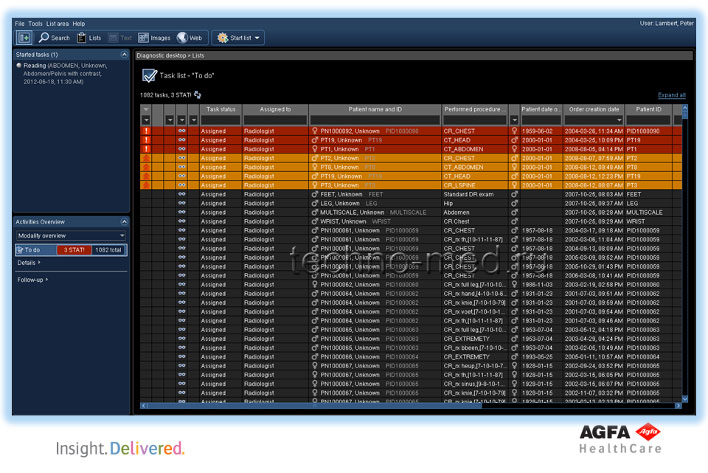

- Поддерживает непрерывный поток операций с изображениями во всех подразделениях предприятия;

- Обеспечивает действие механизма реализации рабочих процессов, основанных на поставленных задачах, соответствующий современным сложным требованиям;

| Дежурный приёмного отделения | Технолог | Рентгенолог | Фонотипист | Клинический врач |